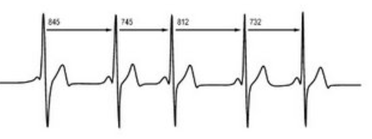

De tijd tussen de hartslagen moet variëren. Onvoldoende variatie kan duiden op vermoeidheid, onvoldoende herstel na inspanning of stress. Met geavanceerde meetapparatuur is men in staat om de hartslagvariatie zichtbaar te maken.Het kent twee systemen:

- Het sympatische systeem (gaspedaal)

- Het parasympatisch systeem (het rempedaal).